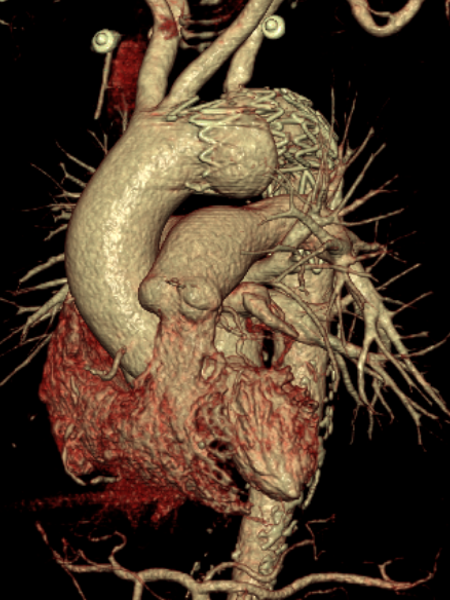

【病例4】

B型夹层TEVAR术中逆撕至升主动脉

再干预方案:首选急诊开放手术修复(升主动脉置换或半弓置换)

逆撕至升主动脉

急诊开放手术